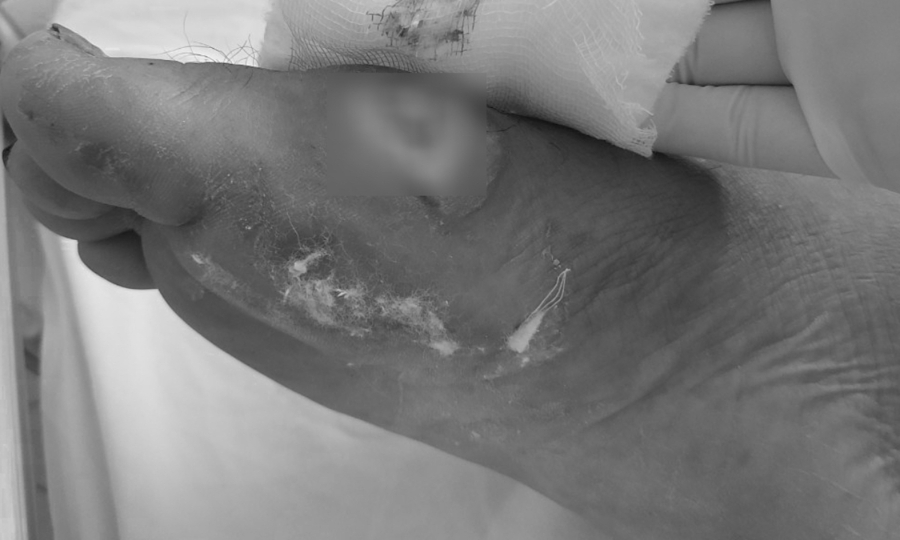

Chân bệnh nhân bị hoại tử do vi khuẩn Burkholderia. Ảnh: Bệnh viện cung cấp.

Sau đợt bão lũ kéo dài từ đầu tháng 10 đến nay, nhiều trường hợp mắc bệnh Whitmore đã gia tăng ở nhiều tỉnh miền Trung. Quảng Trị ghi nhận 24 trường hợp, Bệnh viện Thừa Thiên-Huế tiếp nhận 30 trường hợp … Bệnh viện Đà Nẵng điều trị 29 trường hợp, bệnh nhân chủ yếu đến từ Quảng Nam, Nghệ An, Quảng Ngãi và Đà Nẵng. – Vết thương do áp xe do Whitmore gây ra đã được điều trị. Ảnh: Bệnh viện cung cấp.